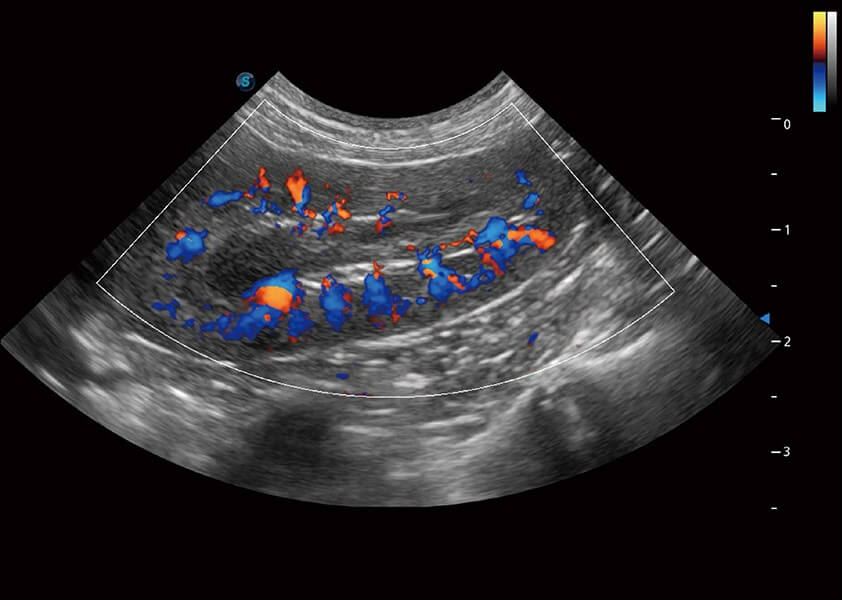

ProPet 60 作為一款高端臺(tái)式動(dòng)物超聲設(shè)備,為動(dòng)物醫(yī)生的日常診斷提供了一系列貼合動(dòng)物臨床需求、解決臨床實(shí)際問題的高級成像功能。憑借全系列高清探頭,滿足醫(yī)生對腹部、心臟、生殖、淺表、肌骨等成像的所有需求,切實(shí)幫助您提升檢查效率,提高診斷信心。